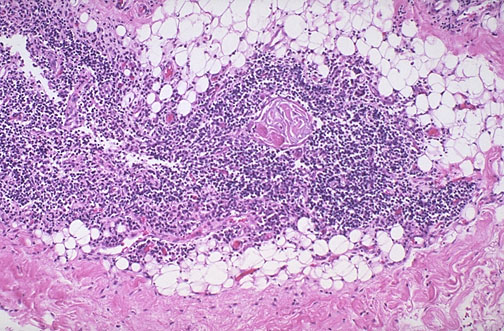

Normal adult thymus is seen at low magnification. Beyond puberty, the thymus continues to atrophy, with decreasing numbers of lymphocytes, so that the adipose tissue becomes more prominent. Occasional Hassall's corpuscles appear the lymphoid areas.